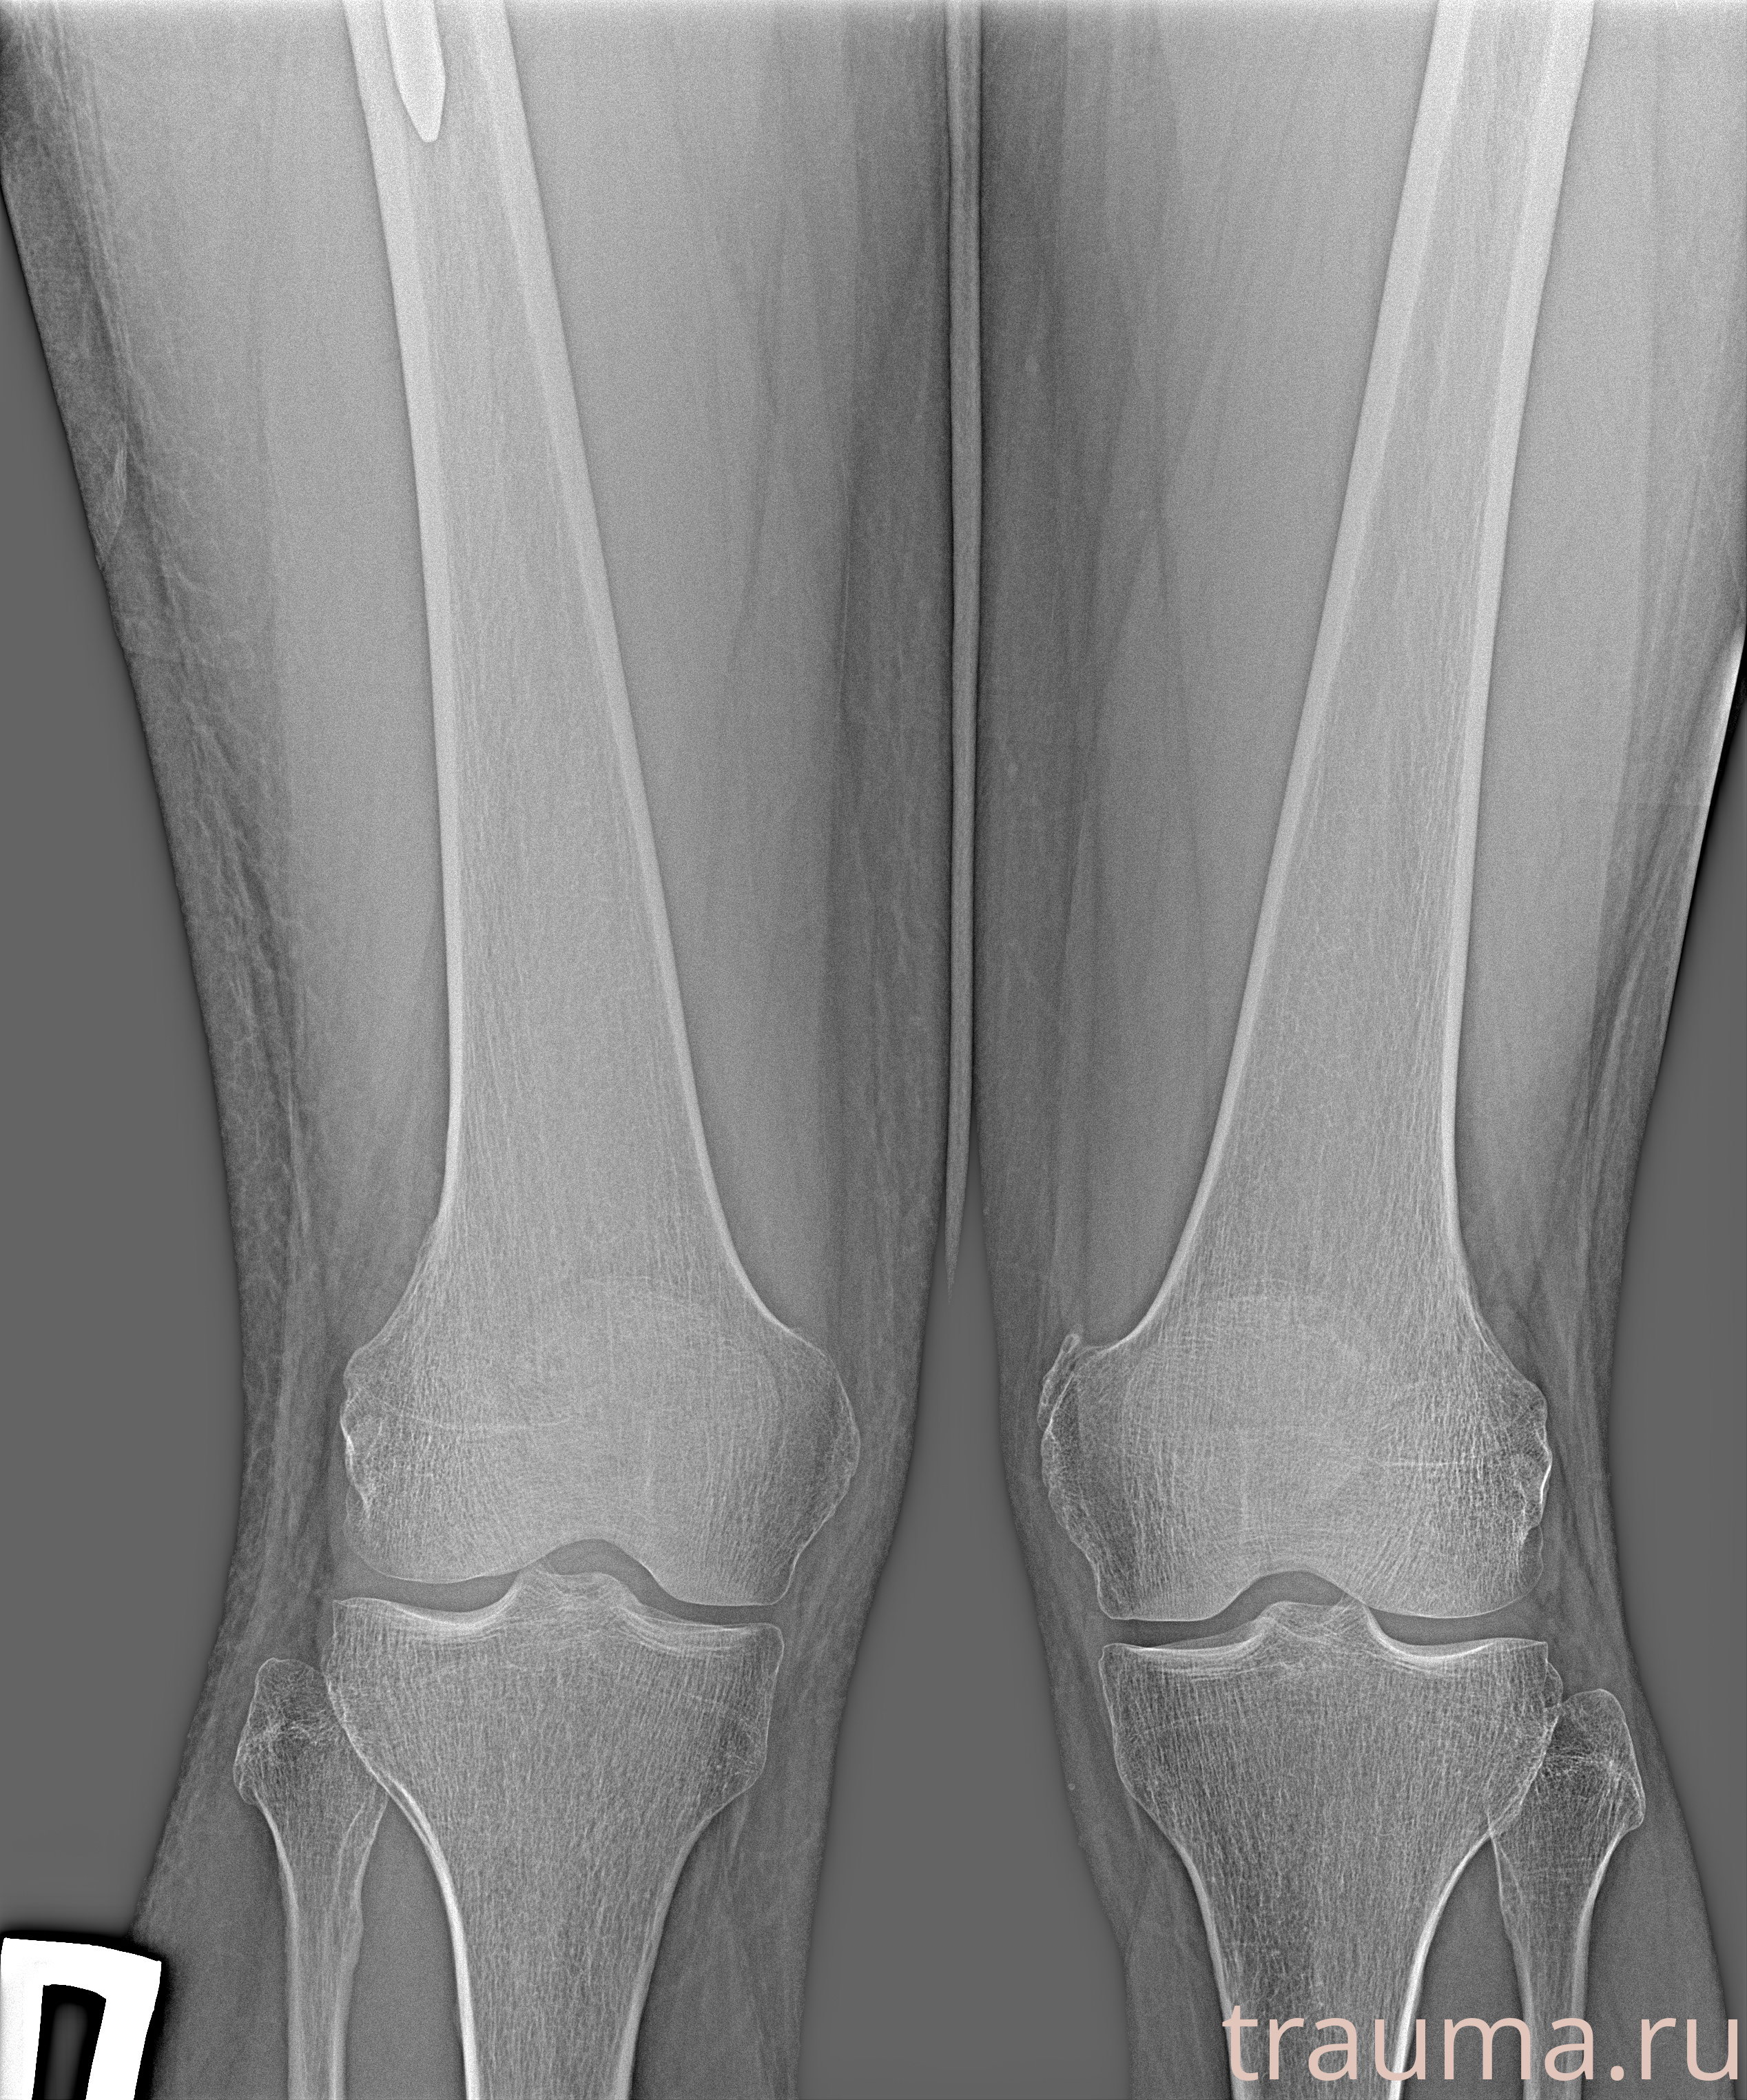

Рентгенограммы

Рентген на дому: по вашему адресу приезжает врач-рентгенолог, травматолог-ортопед с мобильным рентгеновским аппаратом, проводит диагностику травмы или заболевания, делает необходимые рентгенограммы, дает рекомендации по дальнейшему лечению. Получить качественные снимки в домашних условиях возможно благодаря уникальной методике, разработанной МосРентген Центром для института  Склифосовского